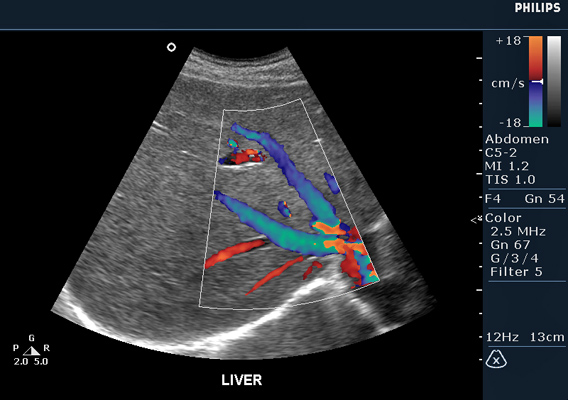

Осмотру подлежат печень, селезенка, желчный пузырь, поджелудочная железа, почки, забрюшинные лимфоузлы, аорта, нижняя полая, воротная и селезеночная вены с проведением допплерометрии и оценкой скоростей кровотока.